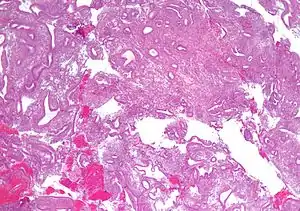

Hiperplasia do endométrio é uma condição caracterizada pela proliferação excessiva das células do endométrio, a camada mais interna do útero. A maioria dos casos de hiperplasia do endométrio resulta de altos níveis de estrogênio combinados com níveis insuficientes de hormônios progestágenos, que geralmente equilibram os efeitos proliferativos do estrogênio sobre o tecido endometrial. Isto pode ocorrer em inúmeras situações, incluindo obesidade, síndrome do ovário policístico, tumores produtores de estrogênio (por exemplo, tumores de células da granulosa) e em certas formulações da terapia hormonal de reposição de estrogênio. A hiperplasia do endométrio é um fator de risco significativo para o desenvolvimento ou mesmo a coexistência de um câncer endometrial.

O diagnóstico da hiperplasia endometrial pode ser feito a partir da biópsia do endométrio, que pode ser realizada ambulatorialmente ou a partir da curetagem da cavidade uterina para a obtenção de tecido endometrial para análise histopatológica. A rotina diagnóstica de doença endometrial pode ser realizada no sangramento uterino anormal ou na presença de células glandulares atípicas no citopatológico do colo uterino.[2]